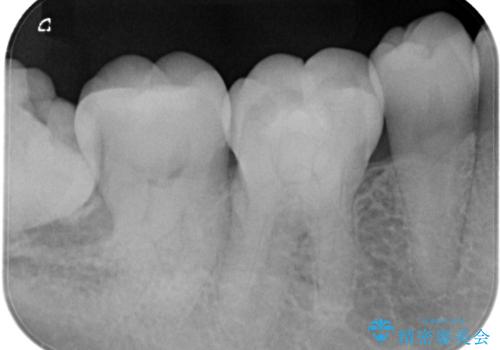

親知らずが原因の深いむし歯

- 検診にて親知らずが原因と思われる深いむし歯を発見し、親知らずを抜歯した後ゴールドインレーにて修復治療を行っております。

ゴールドインレーにて修復を行うことで適合の良い治療を行うことができました。